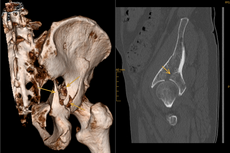

Zur weiterführenden Diagnostik einer Beckenverletzung steht uns modernste radiologische Bildgebung mit 3D-Rekonstruktion zur Verfügung. Auch intraoperativ ist eine 3D-Bildgebung bei laufender Operation möglich. Zur Therapie von vorderen und hinteren Beckenring-Frakturen favorisieren wir Platten-Osteosynthesen offener Reposition, aber auch minimal-invasive Therapieoptionen und transkutane Verschraubungen.

Frakturen der Hüftgelenkspfanne

Frakturen der Hüftgelenkspfanne (Azetabulumfrakturen) sind häufig komplizierte Frakturen. Die Schwierigkeit der Versorgung liegt in der exakten Wiederherstellung der konkaven Gelenkfläche. Auch bei optimaler Versorgung kann sich aus einer Azetabulumfraktur ein frühzeitiger Hüftgelenksverschleiß entwickeln.

Die Therapie-Entscheidung berücksichtigt die individuelle Situation des Verletzten wie Lebensalter, Knochenqualität, körperliche Aktivität u.v.m. und bedarf hoher operativer Erfahrungen. Neben den oben genannten Verfahren kommt auch die sofortige endoprothetische Versorgung mit speziellen Stützschalen in Betracht. Sie gewährleistet gerade bei älteren Menschen eine frühzeitige Mobilisation.